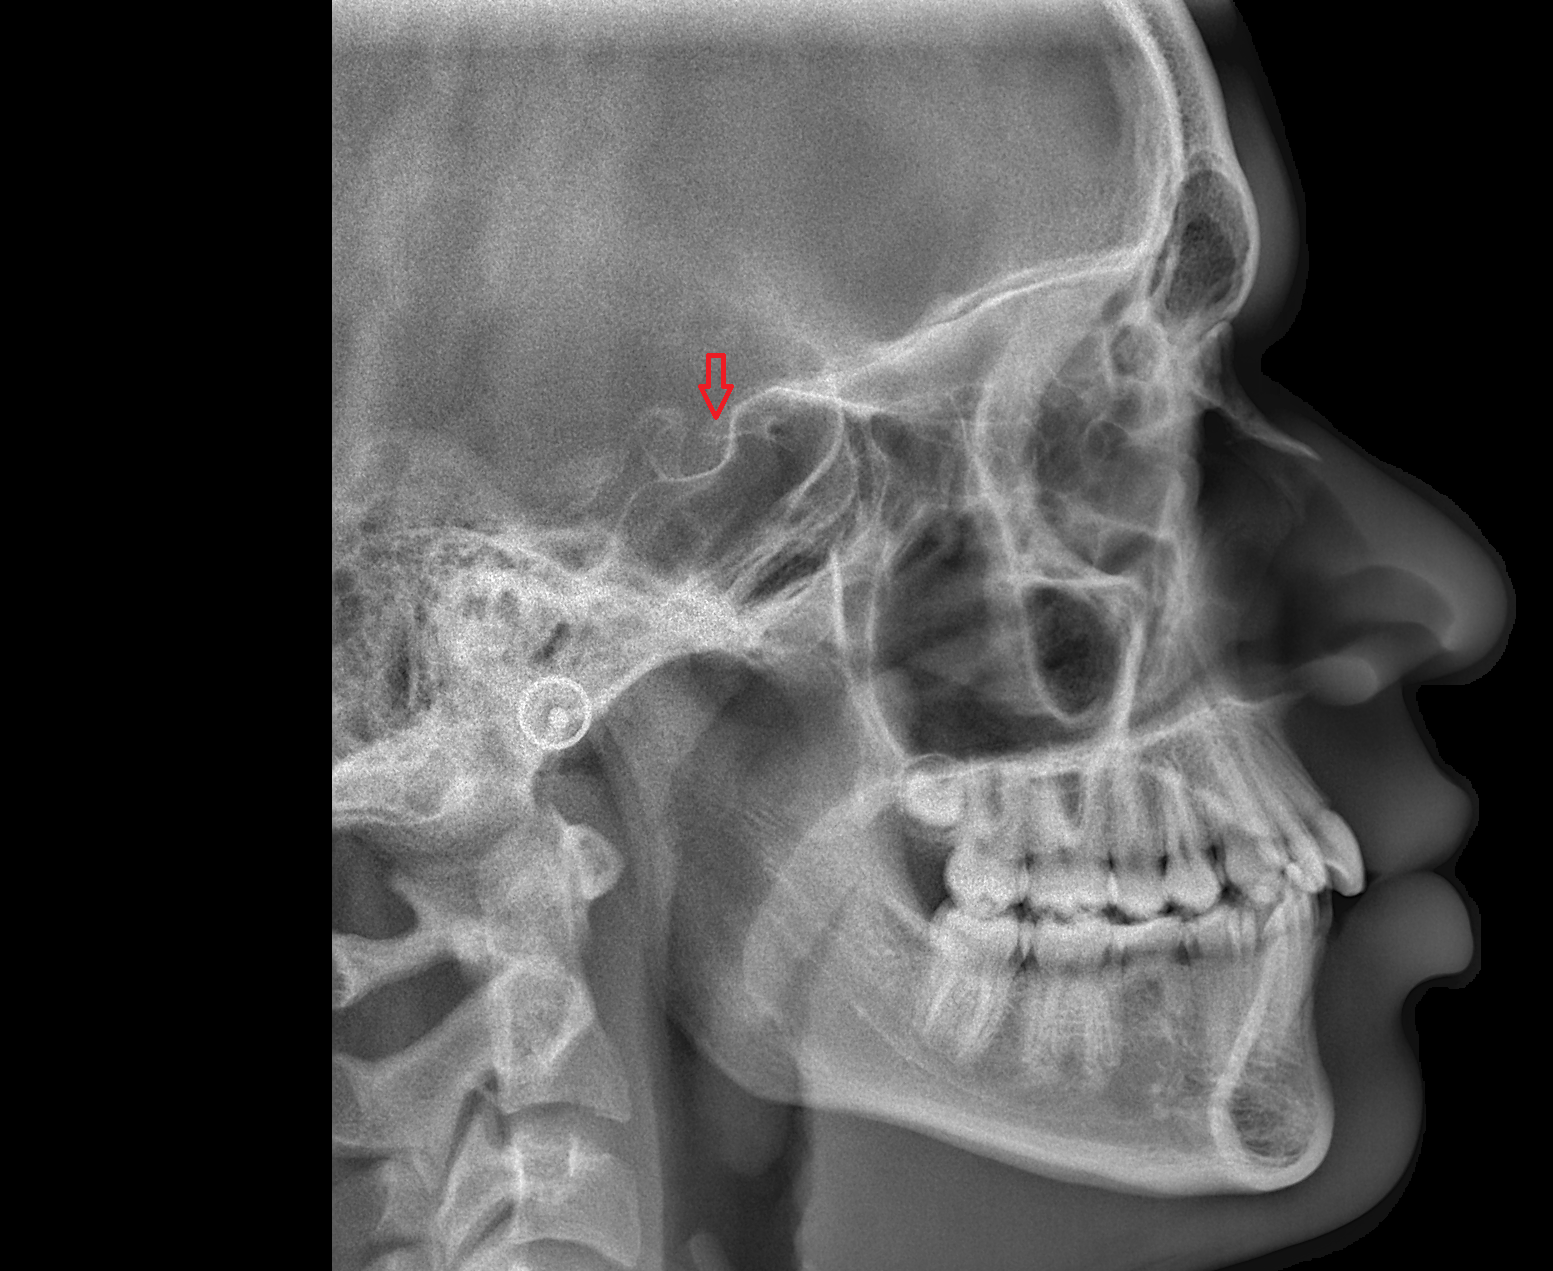

- Temporomandibular joint

- Mandibular condyle

- Mandibular fossa

- Articular eminence

- Articular surface of mandibular fossa

- Articular tubercle